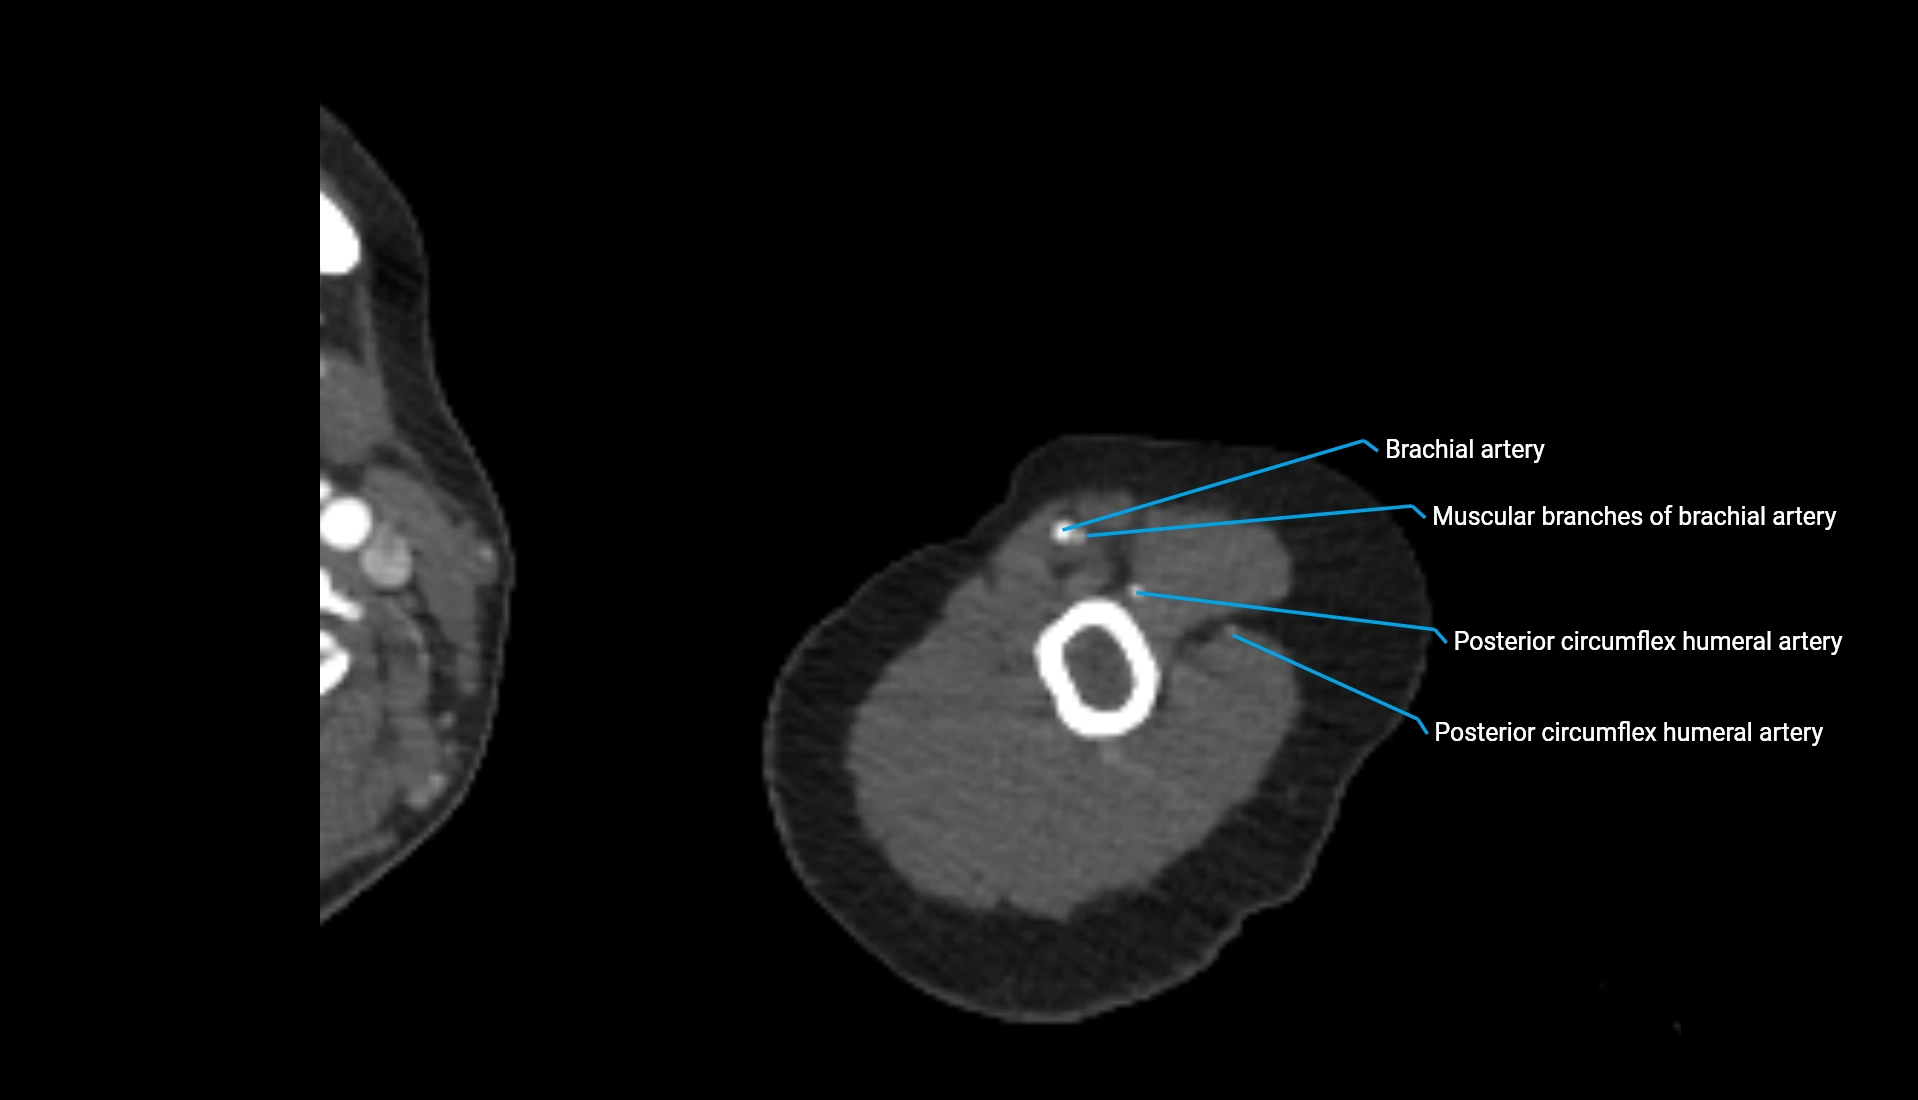

CT Appearance

Non-Contrast CT:

• Cortex: High-density, sharply defined

• Subchondral bone: Dense cancellous matrix

• Articular surface: Smooth concave contour articulating with the capitellum

• Excellent for evaluating bone integrity, alignment, and subtle fractures